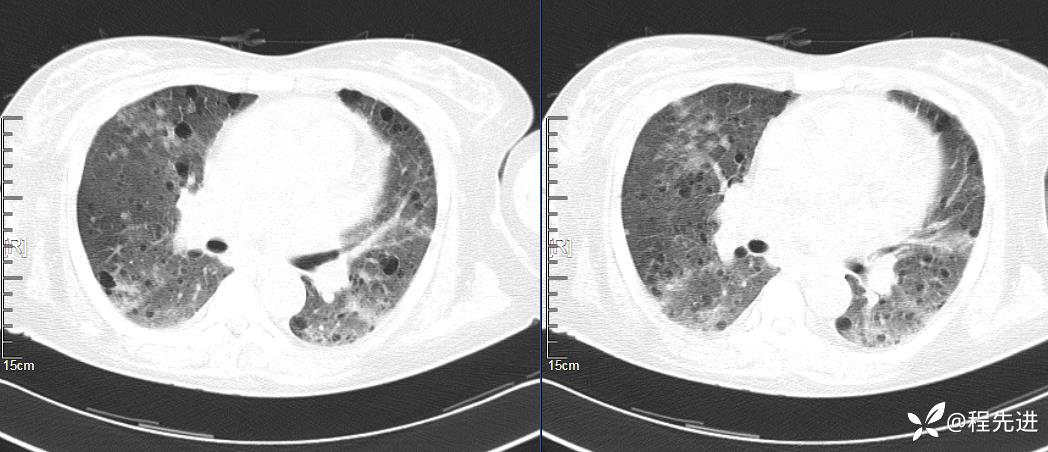

CT平扫(纵隔窗无特殊,就不上传了):

2、本例肺气囊分布有什么特点?肺气囊有无小叶核心?有没有间质纤维化及伴发结节?